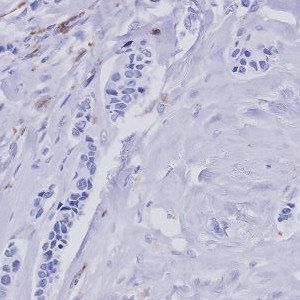

Figure 3

Breast tissue with CD163 negative nuclei.